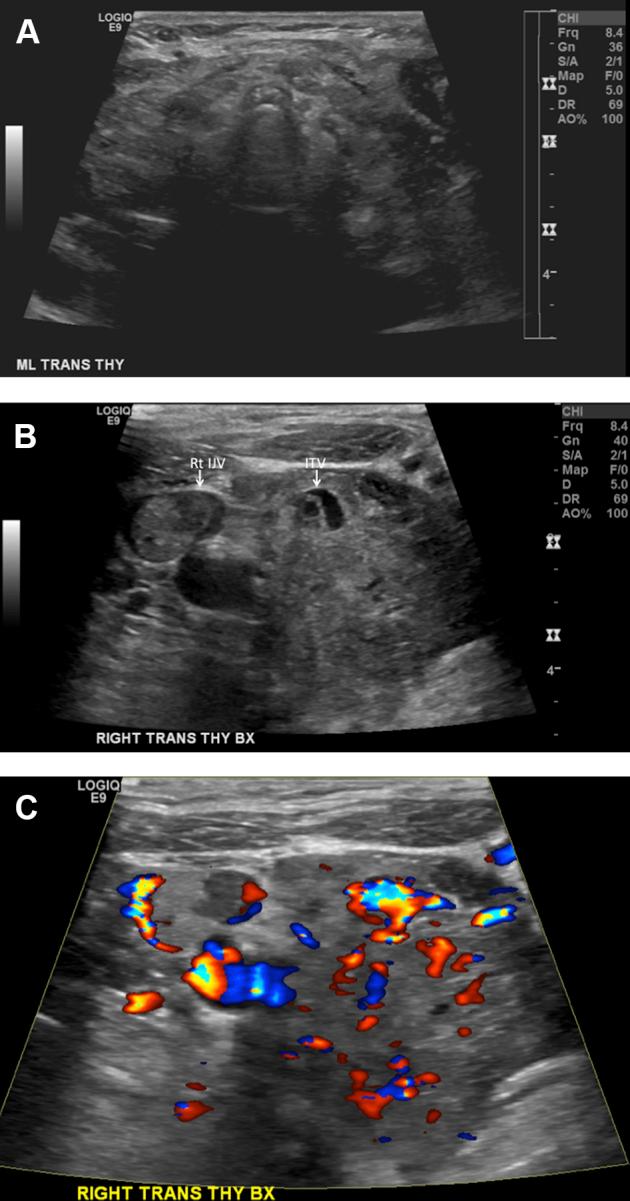

Diffuse thyroid metastases and bilateral internal jugular vein tumor thrombus from renal cell cancer.

Renal cell cancer rarely metastasizes to the thyroid gland, and it has been reported to present as a solitary mass. We present a case of diffuse thyroid cancer metastases from renal cell cancer. Bilateral internal jugular vein tumor thrombi were also present. To the best of our knowledge, this is the first description of diffuse thyroid metastases from renal cell cancer in the English literature. Renal cell cancer metastases should be considered in the differential of thyroid imaging abnormalities arising in the setting of known renal cell carcinoma, particularly late in the course of disease. This is frequently associated with internal jugular vein thrombi, which should be evaluated with an abnormal thyroid. Thyroglobulin levels are usually normal in such patients.